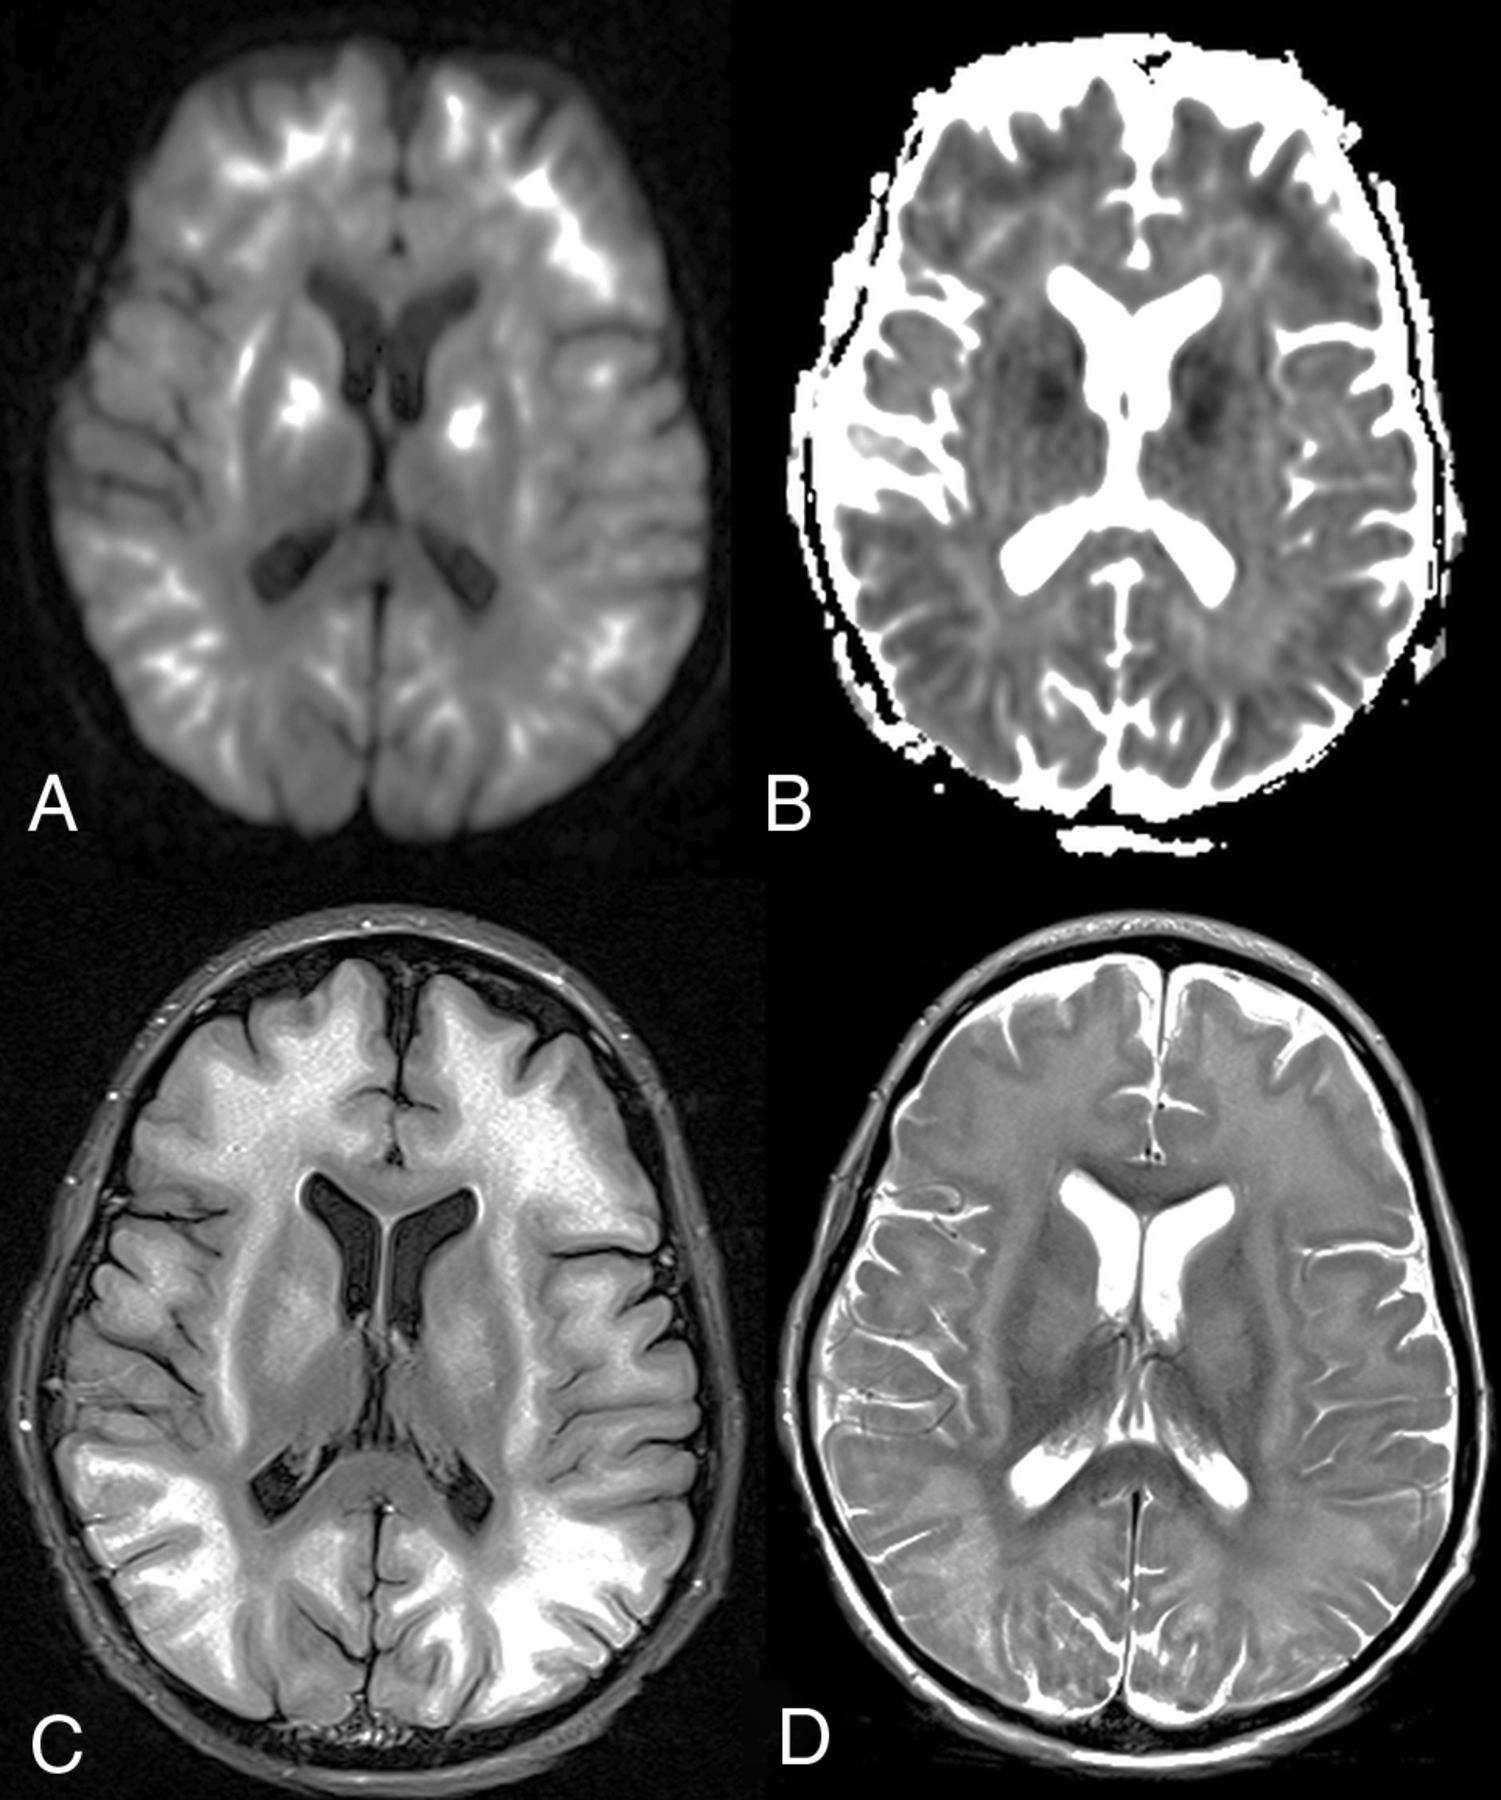

A 10-year-old boy with fludarabine-related PATL (patient 11). Axial DWI (A) and ADC map (B) show symmetric, extensive, and confluent diffusely reduced diffusion with the corresponding hyperintensity on axial FLAIR (C) and T2WI (D) in the subcortical WM and basal ganglia. The child died 7 days after the insult, with the ATL outcome score being 4 (ie, severe outcome).

An 11-year-old boy with methotrexate-induced PATL (patient 5). Axial DWI (A) and ADC map (B) show unilateral reduced diffusion within the deep left frontoparietal PVWM without significant corresponding hyperintensity on an axial FLAIR image (C). The patient had moderate long-term neurologic sequelae, with the ATL outcome score at 1 month being 2. An ADC map (B) illustrates the placement of ROIs for the measurement of ADC values, as well as to determine the %ADCR. Such ROIs were located in the affected WM lesion (red ROI) and nonaffected WM (NAWM) (orange ROI).